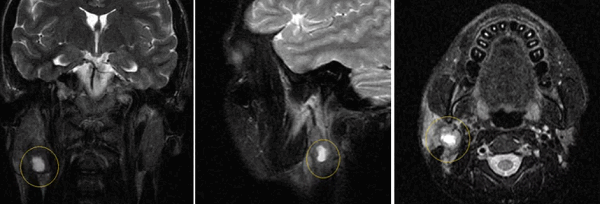

МРТ слюнных желез что показывает

МРТ слюнных желез — неинвазивный метод визуализации мягких тканей ротовой полости, в частности органов, вырабатывающих слюну. Позволяет оценить характер работы желез, степень сохранности секреторной активности, присутствие инородных тел и опухолей. В деле раннего выявления патологий указанного участка МРТ слюнных желез находится вне конкуренции: это единственная безопасная методика, обладающая достаточной информативностью.

МРТ слюнных желез с контрастом

МРТ с контрастом дает возможность на ранних стадиях выявить опухолевые образования в структуре слюнных желез, определить их размеры, локализацию, форму, строение, степень васкуляризации (кровоснабжения). Это требуется, в том числе, перед проведением хирургического лечения для определения объемов вмешательства и стратегии терапии, биопсией. На основании данных МРТ с контрастом можно сделать предварительный вывод о злокачественности или доброкачественности новообразования.